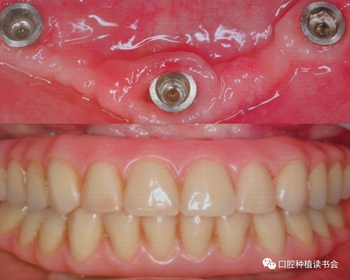

技師在模型上完成預(yù)成支架+樹脂義齒的制作,戴入口內(nèi)完成即刻負重,手術(shù)后兩個月觀察種植體軟硬組織整合良好(圖9、10)。

圖9 手術(shù)當(dāng)天制作的正式修復(fù)體

圖10 手術(shù)后兩個月觀察種植體軟硬組織整合良好,修復(fù)體使用良好

目前全世界有5個臨床中心,針對110名患者采用Trefoil下頜無牙頜種植修復(fù)理念,進行5年的追蹤;從目前以發(fā)表的40名患者,共計120顆植體,1年的隨訪種植體成功率為97.6%。通過繼續(xù)的觀察,與現(xiàn)有的種植治療方式相比,Trefoil下頜無牙頜種植修復(fù)的臨床效果將進一步得到確認。